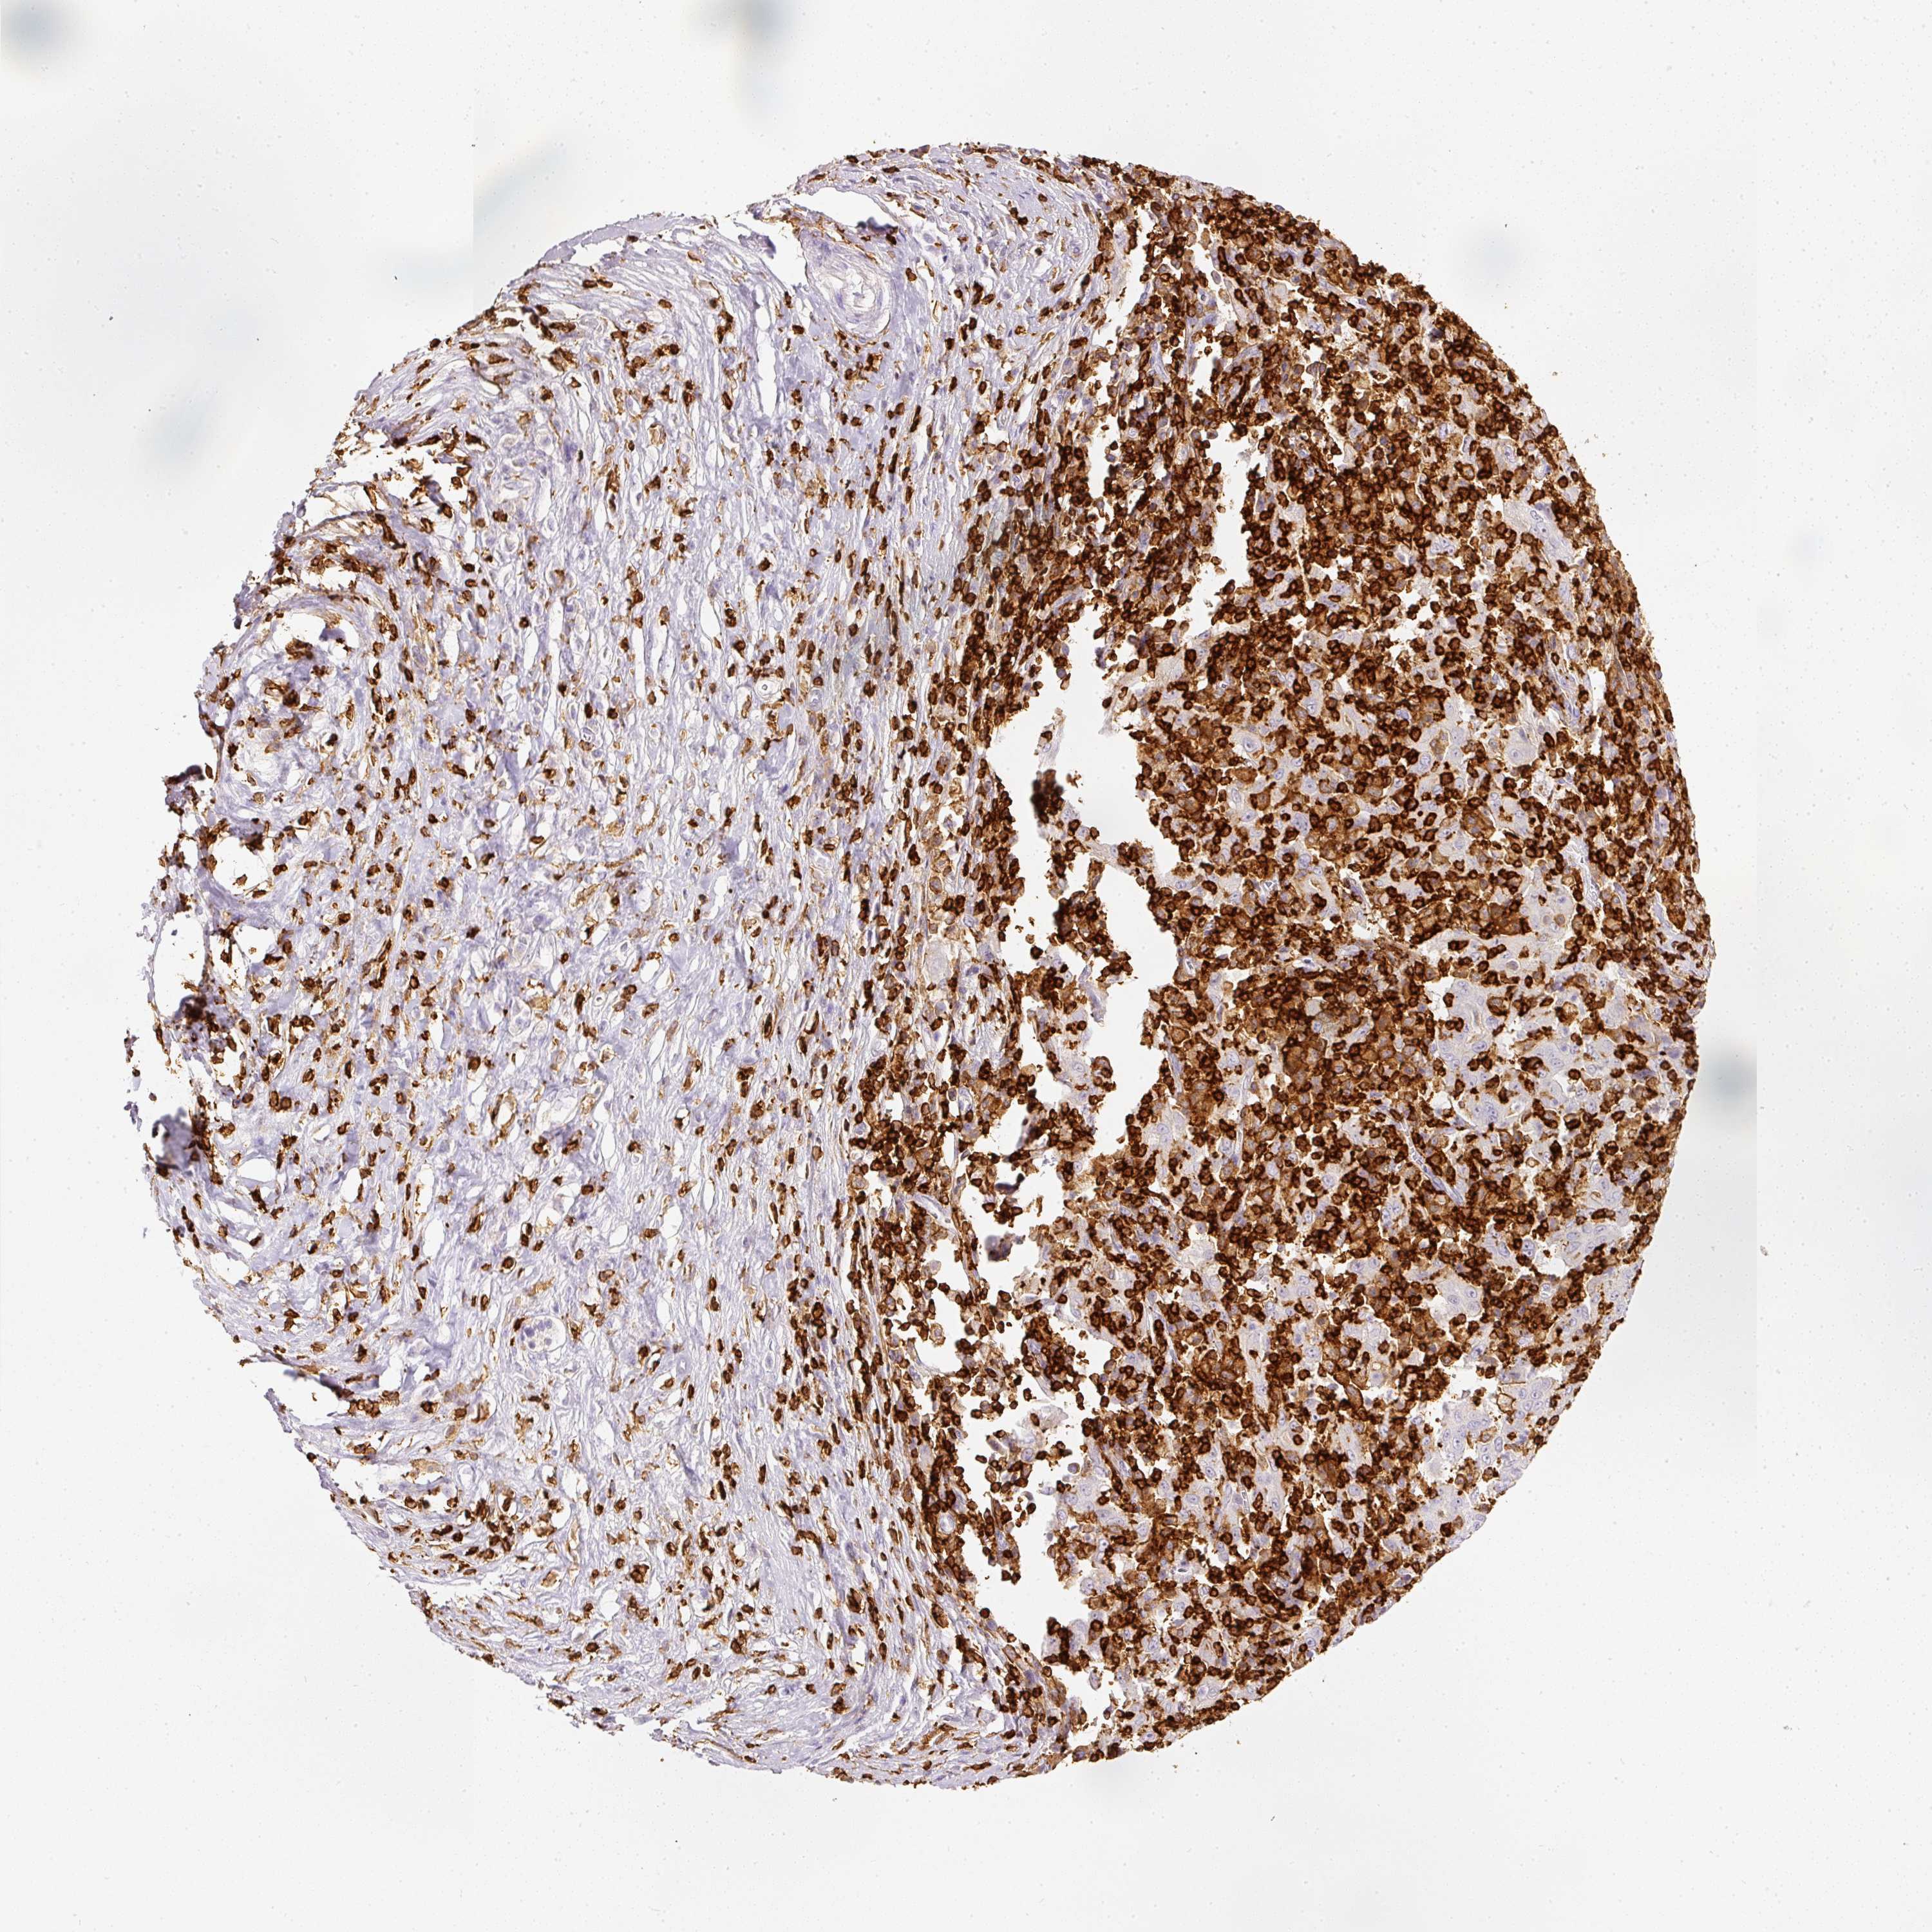

PANCREATIC CANCER - Protein expressioni

A mouse-over function shows sample information and annotation data. Click on an image to view it in a full screen mode. Samples can be filtered based on level of antibody staining by selecting one or several of the following categories: high, medium, low and not detected. The assay and annotation is described here.

Note that samples used for immunohistochemistry by the Human Protein Atlas do not correspond to samples in the TCGA dataset.

Antibody stainingi

Antibody staining in the annotated cell types in the current human tissue is reported as not detected, low, medium, or high, based on conventional immunohistochemistry profiling in selected tissues. This score is based on the combination of the staining intensity and fraction of stained cells.

Each image is clickable and will lead to virtual microscopy that enables deeper exploration of all samples and also displays staining intensity scores, fraction scores and subcellular localization as well as patient and tissue information for each sample.

Antibody HPA018849

Antibody HPA019536

Antibody CAB033987

Staining

High

Medium

Low

Not detected

Intensity

Strong

Moderate

Weak

Negative

Quantity

>75%

75%-25%

<25%

None

Location

Nuclear

Cytoplasmic/membranous

Cytoplasmic/membranous,nuclear

Adenocarcinoma, NOS